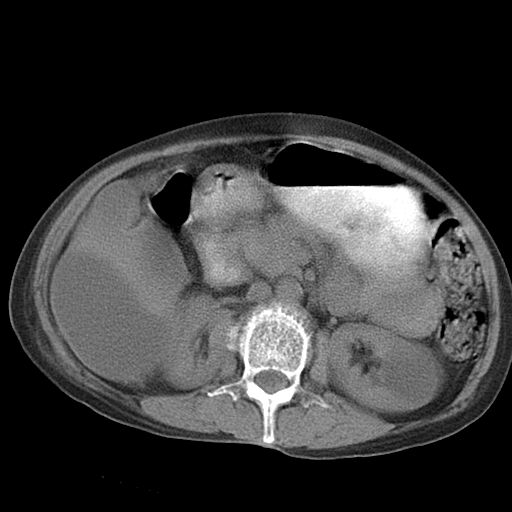

以下是引用dyqct在2006-12-7 21:08:00的发言:[br]考虑:1、肝内外胆管多发性结石伴肝左叶外侧段肝萎缩;[br] 2、右膈下多发脓肿;[br] 3、右侧少量胸腔积液、斜裂积液;[br] 4、左肾囊肿。

以下是引用jiazh在2006-12-7 20:37:00的发言:[br]肝脏周围半狐形低密度影,肝脏表面受压推移,考虑膈下脓肿可能性大;2、右侧胸腔积液

以下是引用拾荒者在2006-12-7 21:44:00的发言:[br]肝内外胆管多发结石,右膈下多发脓肿,右胸膜腔及叶间裂积液,左肾囊肿。[br] [br]